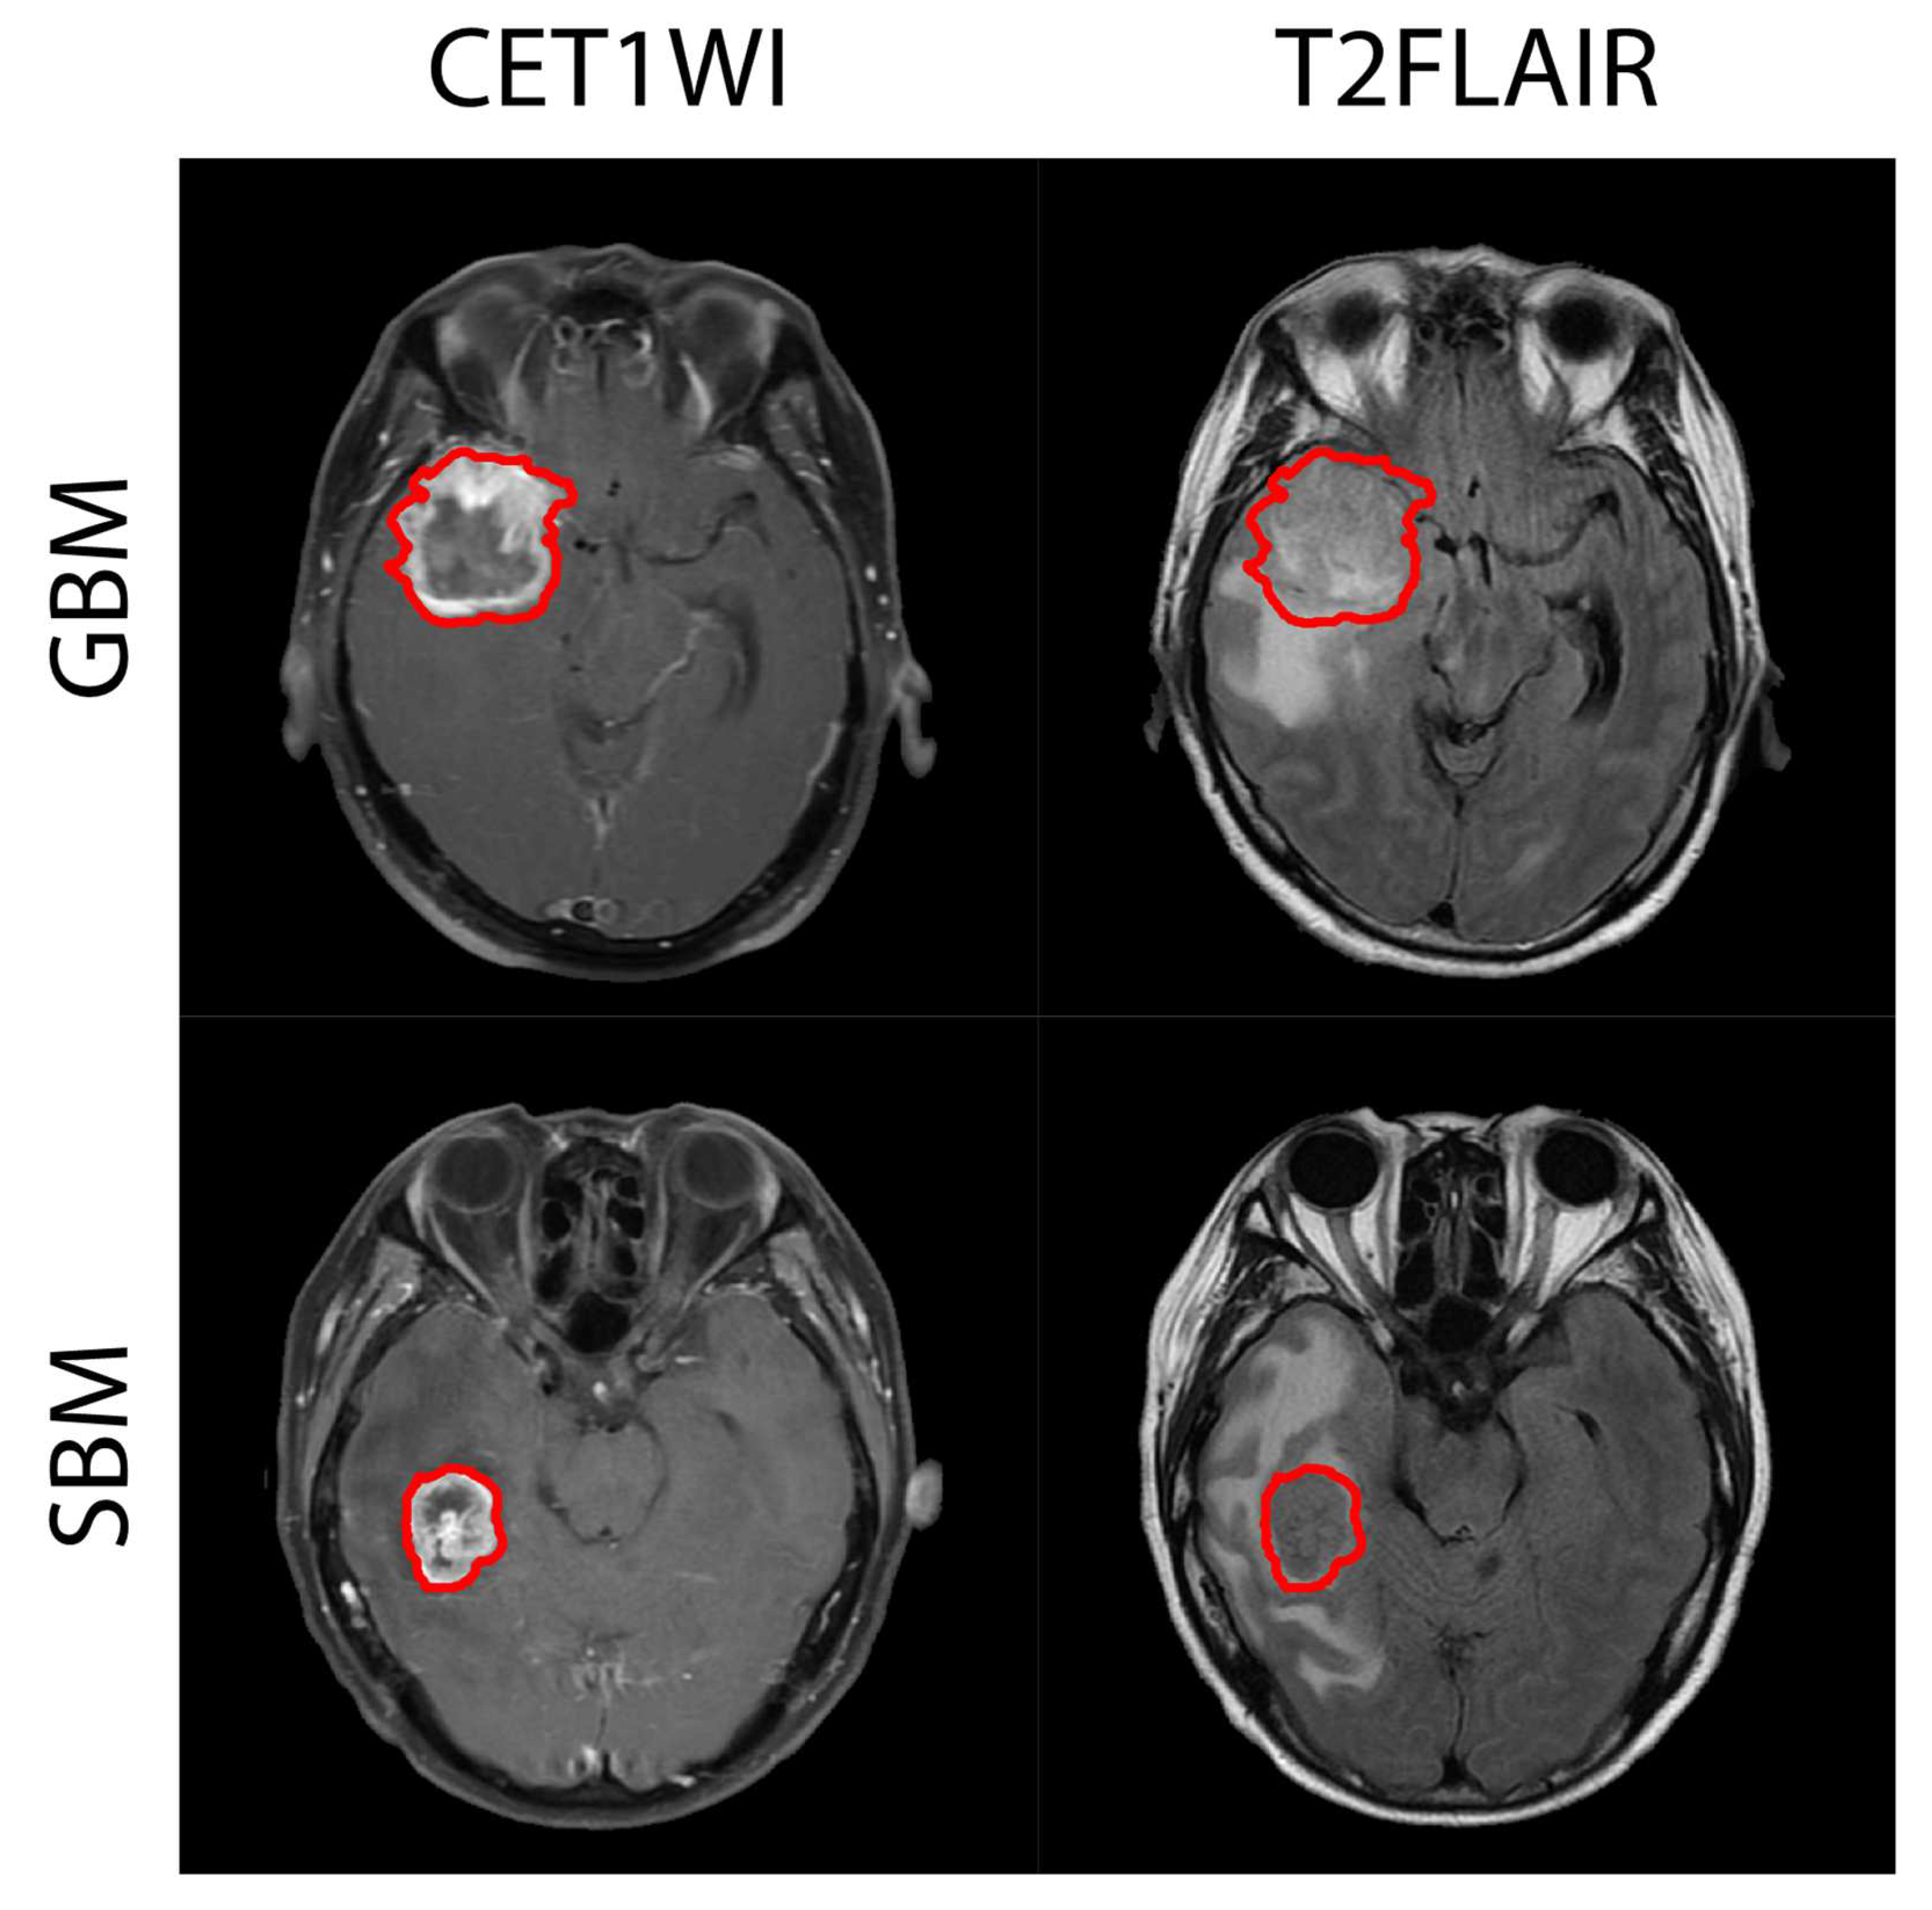

- Maurer, M.H.; Synowitz, M.; Badakshi, H.; Lohkamp, L.N.; Wüstefeld, J.; Schäfer, M.L.; Wiener, E. Glioblastoma multiforme versus solitary supratentorial brain metastasis: Differentiation based on morphology and magnetic resonance signal characteristics. RöFo-Fortschr. Auf Dem Geb. Röntgenstrahlen Bildgeb. Verfahr. 2013, 185, 235–240. [Google Scholar] [CrossRef] [PubMed] [Green Version]

- Chen, X.Z.; Yin, X.M.; Ai, L.; Chen, Q.; Li, S.W.; Dai, J.P. Differentiation between brain glioblastoma multiforme and solitary metastasis: Qualitative and quantitative analysis based on routine MR imaging. AJNR Am. J. Neuroradiol. 2012, 33, 1907–1912. [Google Scholar] [CrossRef] [PubMed] [Green Version]